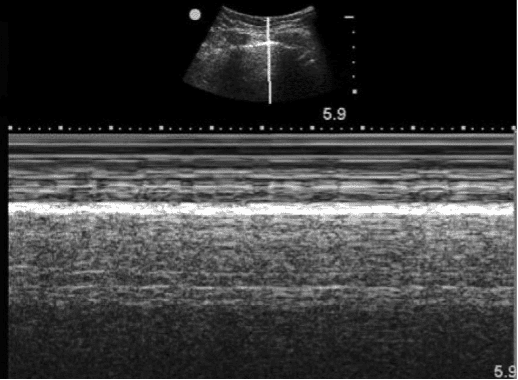

- Seashore sign (M-mode): A wavy pattern that reflects normal pleural movement.

Figure 3. Seashore sign on M-mode.